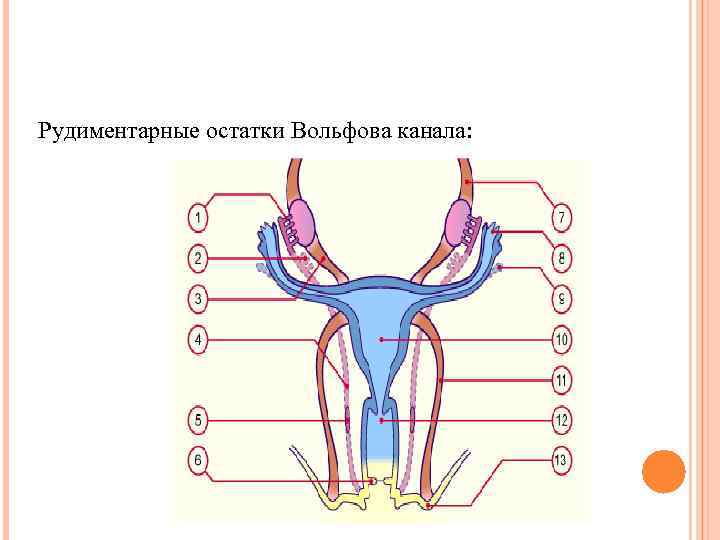

Рудиментарные остатки Вольфова канала:

Рудиментарные остатки Вольфова канала: